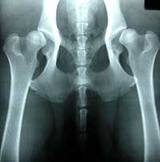

Bad hips Example - 2013-08-16 15:40:35